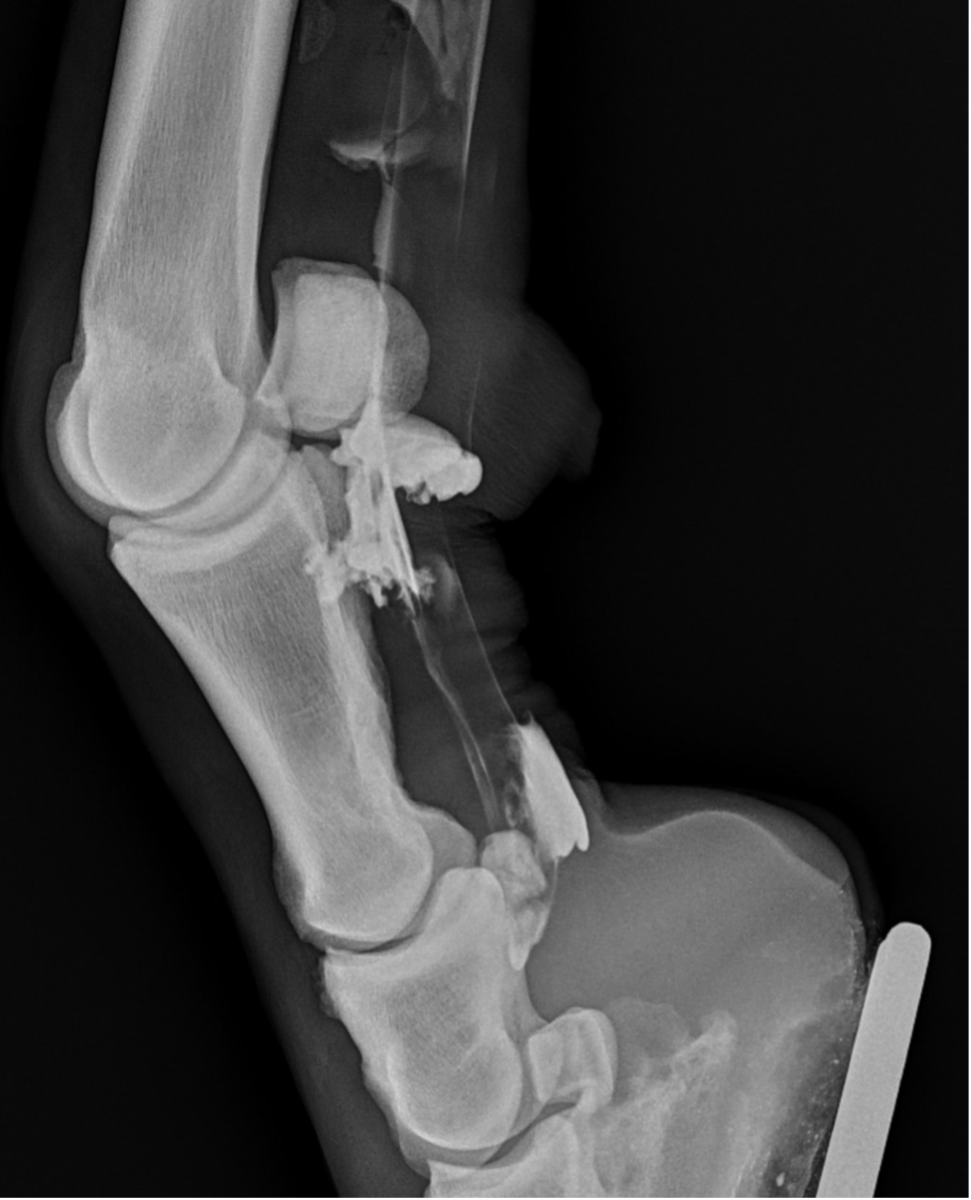

Upon further examination, contrast radiographs and ultrasound scans failed to identify any significant abnormalities apart from swollen synovium within the DFTS. To address this issue, our veterinary team administered 5mg of triamcinolone acetonide along with 20mg of HA, complemented by a compression wrap. Subsequently, the horse underwent a two-week confinement period in a small yard, followed by gradual reintroduction to exercise through 10 minutes of hand walking twice daily, with the distal limb wrapped for additional support.

However, when the condition resurfaced, our client chose to pursue tenoscopy, which fortunately revealed no clinically significant abnormalities. Following the procedure (2-weeks post-surgery), 2ml (50mg) of Arthramid was injected into the sheath, followed by two weeks of hand walking and a seamless transition back to regular riding activities.